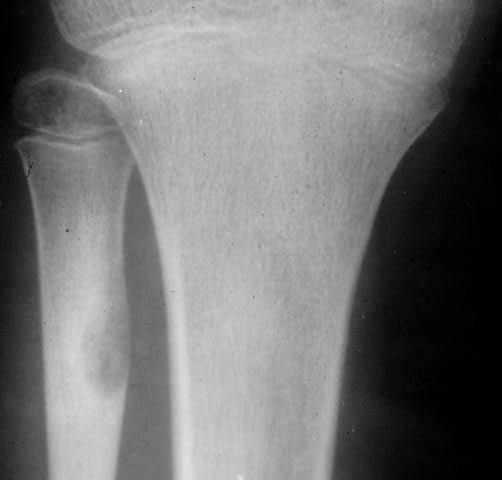

Your healthcare provider will first ask about your symptoms and do a physical examination. They may ask you questions about the pain, such as: How long you’ve had pain. How severe the pain is. What helps to relieve the pain. Whether you’ve had an injury to the painful area. If your provider suspects an osteoid osteoma, they may suggest tests including: X-ray: This diagnostic imaging test creates pictures of your bone. In an X-ray, an osteoid osteoma will appear as thickened bone that surrounds a small central core. Three-phase bone scan: During a three-phase bone scan, your provider: Injects a radioactive material (radiotracer) into your vein. A camera detects this radiation and takes pictures of the radiotracer in your bone. The camera takes a picture of the blood that builds up in your bone and soft tissue. The camera takes another set of images of the same location two to three hours after the injection. This scan helps your provider find the exact location of the tumor. CT (computed tomography) scan or magnetic resonance imaging (MRI): A CT scan shows an image of your bone and can help identify an osteoid osteoma. An MRI is less accurate in showing an osteoid osteoma but can help rule out cancer. Biopsy: During a biopsy, your provider removes a sample of the tumor. They look at this tissue under a microscope for signs of an osteoid osteoma. This biopsy also helps them to rule out other conditions. Blood tests: Your provider may take blood tests to rule out an infection.